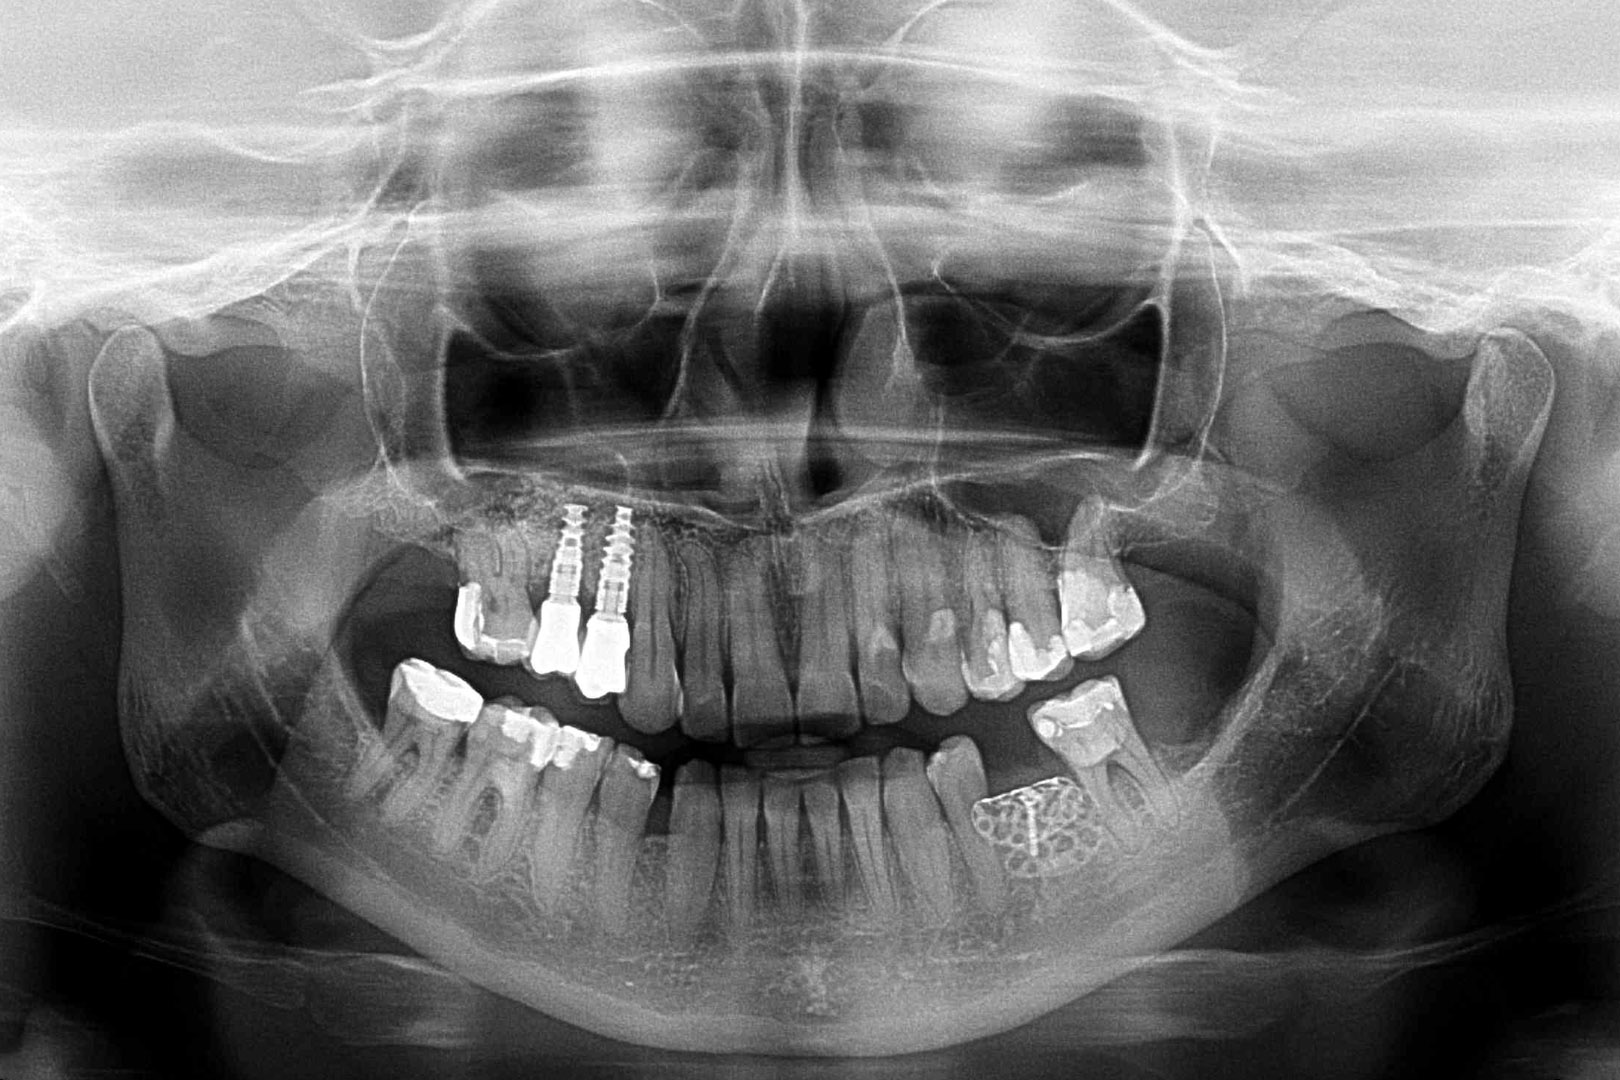

Przed podjęciem leczenia należy określić stopień zaniku kości szczęk oraz żuchwy. W tym celu przeprowadza się badanie kliniczne oraz odpowiednią diagnostykę obrazową pacjenta. Uwzględnia ona zdjęcie panoramiczne OPG jako podstawę dwuwymiarowego obrazowania podłoża kostnego oraz możliwe jest badanie tomograficzne CT lub bardziej precyzyjna tomografia stożkowa CBCT. Opcjonalnie wykorzystywana diagnostycznie tomografia pozwala na bardziej wnikliwą ocenę stopnia zaniku kości w trójwymiarowym, przestrzennym obrazie.